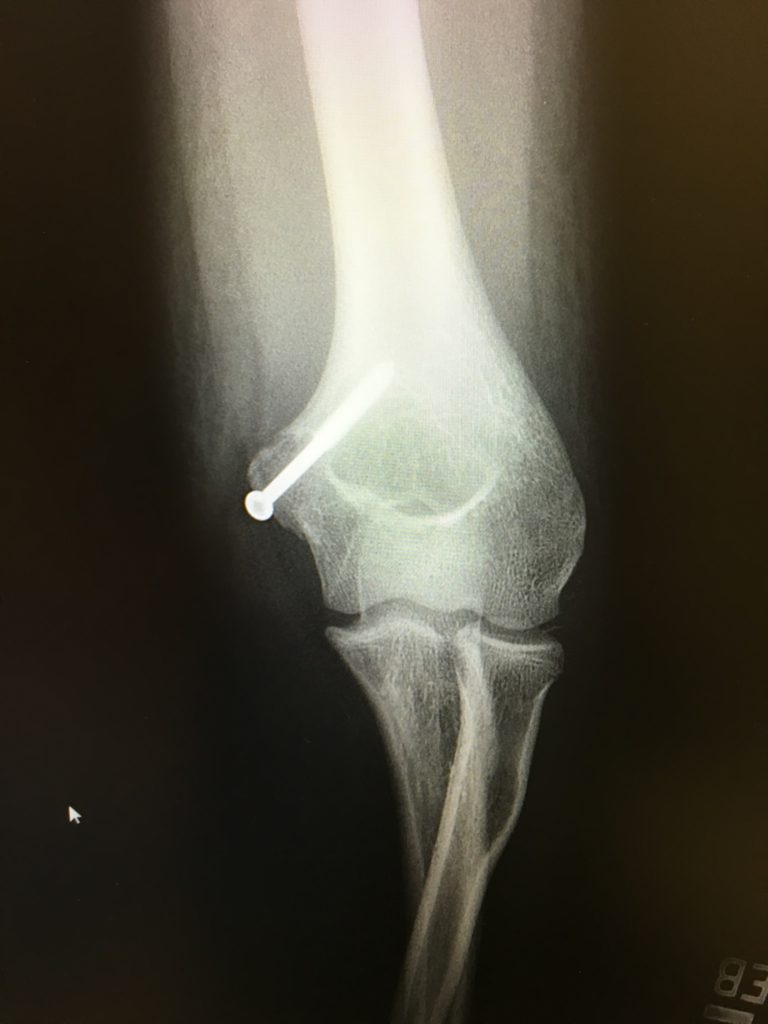

I was a member of a nationally ranked swim team and had just won the Met PGA golf 9-hole Championship.In September of 2013, I suffered a major elbow injury. Dislocating my left elbow by landing on an out-stretched arm on a trampoline, I managed to rip my medial epicondyle completely off the humerus, damaging my tendons and ligaments, and displacing the ulnar nerve. The dislocation

completely bent my elbow in the exact opposite direction of its normal

position! I was in pain and devastated.

Dr. Green took care of me at HSS and reconstructed my elbow, screwing the broken bone back in place and repairing and re-positioning my tendons and

nerve. Dr. Green gave me great care, lots of reassurance and